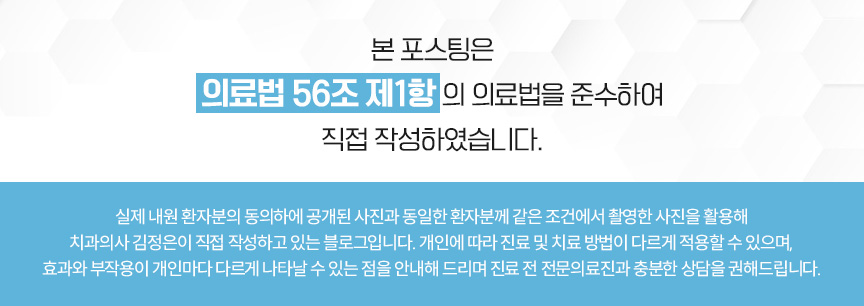

정밀한 검사를 위해

엑스레이를 비롯한 치근단 엑스레이,

턱관절 검사를 통해

치아 교정을 하여도

괜찮은지 확인하는 과정을 걸쳤습니다.

세팔로 사진과 측면 사진을 보았을 때

전보다 안정적으로 입술과 심미선의 거리가

확보된 것을 확인할 수 있었습니다.